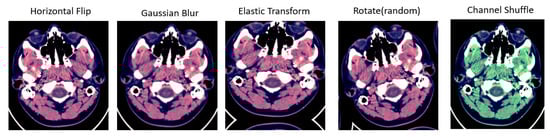

A technique of image augmentation was applied to the dataset in order to enhance the efficiency and robustness of the model training. We used Python’s (version 3.10) augmentation module and TensorFlow’s image data generator API (version V2.13.0) in this study. The selected augmentation techniques are described and illustrated in Table 2 and Figure 4.

Figure 4.

Different types of augmentation used for training data. First image shows the horizontal flip operation applied over the input image; second image is Gaussian blur operation used for augmentation; Elastic transform and rotation operation are applied in third and fourth images; fifth image shows the channel shuffling applied over the input image.